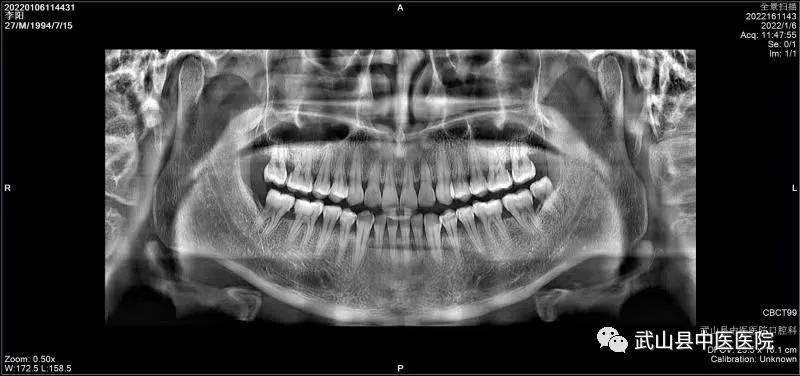

为了更好地服务全县人民,满足人民群众口腔健康需求,实现“口腔健康、全身健康”的目的。武山县中医医院口腔科引进集全景、头颅、CBCT功能于一体的三合一口腔CBCT设备,该设备可以清晰地显示牙齿颌骨的细微结构及牙体牙髓牙周组织,进一步增强了县中医医院口腔科诊疗水平 。

CBCT的应用领域非常广泛,可以运用于口腔学科的各个细分领域,包括种植、正畸、口腔颌面外科、牙体牙髓病、牙周病、颞下颌关节疾病等细分领域。三合一口腔CBCT具有自动咬合定位、三点头颅定位系统、主动侦测颌弓形态、快速投照功能,是更加精细化、专业化的诊断工具,适用于颌骨骨折、骨质破坏(肿瘤、囊肿、骨髓炎、骨结核)、牙齿损伤(牙折、牙脱位)、阻生牙拔除前的治疗计划,为检查修复的牙体邻面及旧修复体周围牙体组织有无龋坏、牙周组织的损害、牙槽骨吸收情况、根管治疗情况、根尖病变情况、牙体发育异常的诊断提供依据。